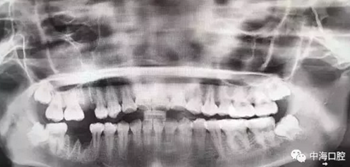

由于智齒的生長位置特殊,導致了拔除難易不同,如智齒出現(xiàn)橫著長或者靠近牙神經的話,則難度會較高,一般人只需拍個口腔全景片,但相對于智齒靠近神經管的情況,還可能需要拍CT,這都很考驗牙醫(yī)的技術。

拔牙非小事,請不要拿成本衡量牙醫(yī)的價值!

下面這兩張圖,據(jù)說拔牙費時1.5小時,收費14000元。